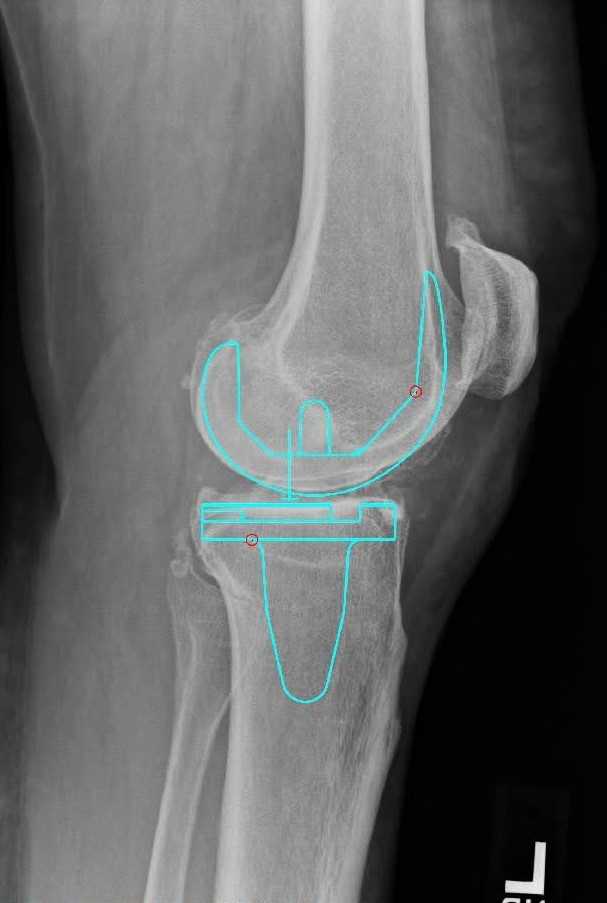

Pre-op X-Rays

Figure 1. Pre-op x-rays.

Equipment

- Attune system with a size 4 femoral component

- Size 5 tibia with 4x7 fixed bearing cruciate retaining insert

- 38 mm all polyethylene patellar button